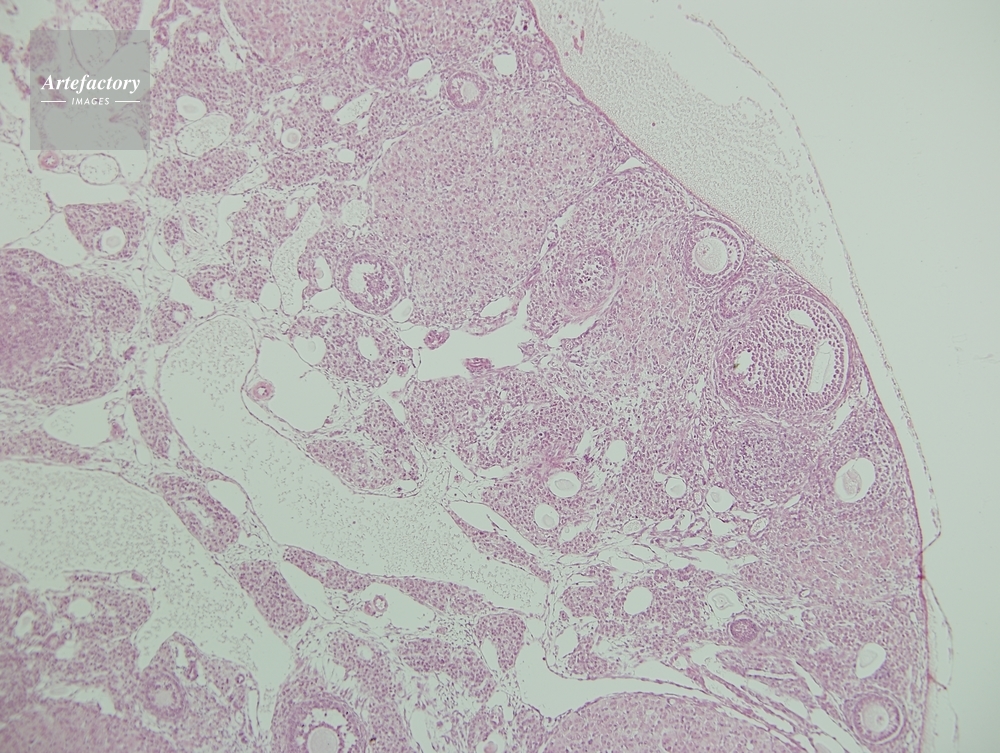

| 作品タイトル | マウス,卵巣 | モデルリリース | なし | |

| 作家 | OLYMPUS CORPORATION Technolab | プロパティリリース | なし | |